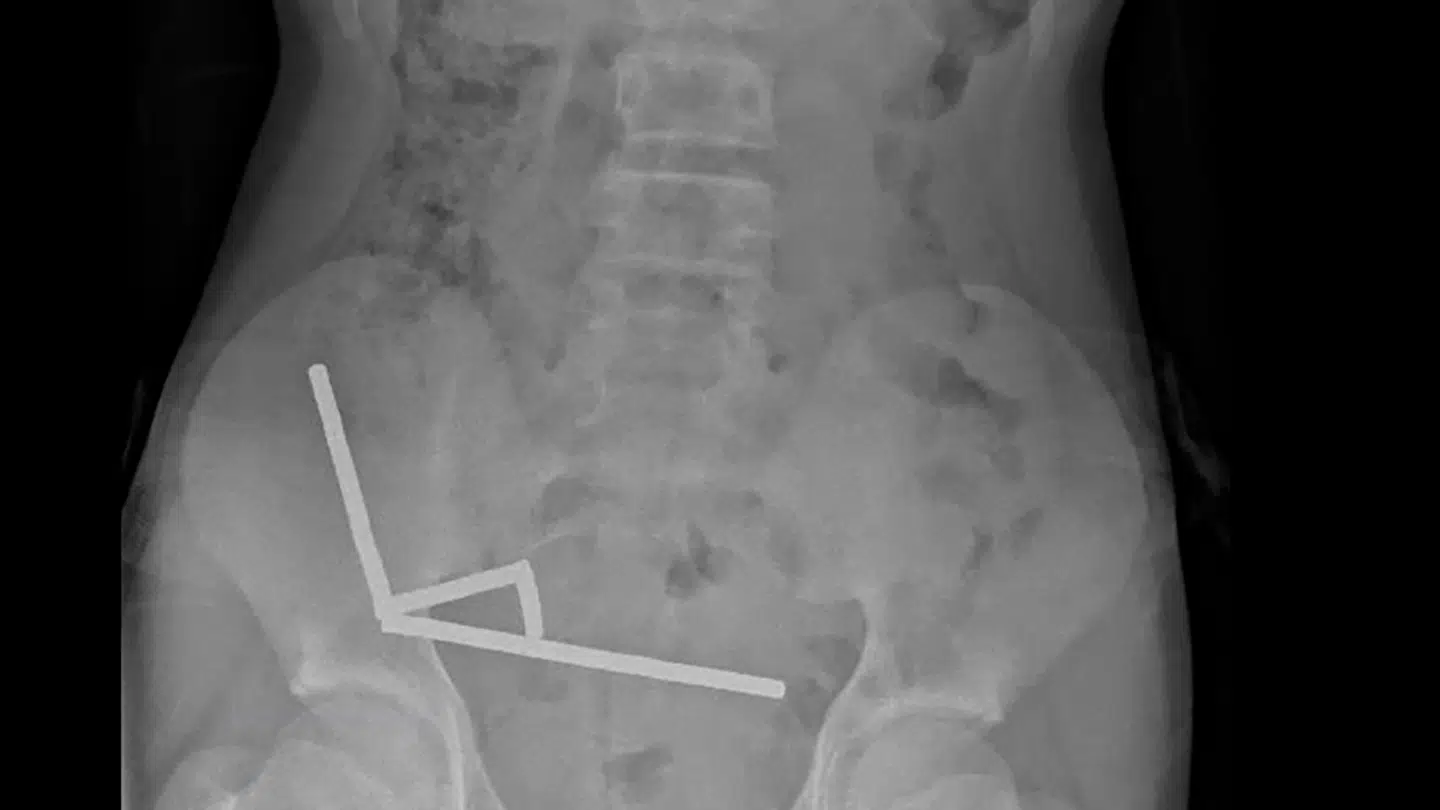

For i maven på den 13-årige dreng fra New Zealand kunne lægerne se fire lige linjer i hans tarme.

»De så ud til at være i separate dele af tarmen, der var klæbet sammen på grund af de magnetiske kræfter,« lyder det i en lægerapport om sagen fra New Zealand Medical Journal, skriver både AFP og ABC News.

I lægerapporten fremgår det, at trykket fra magneterne havde forårsaget nekrose – vævsdød – i fire områder af drengens tyndtarm og blindtarm, som er en del af tyktarmen.